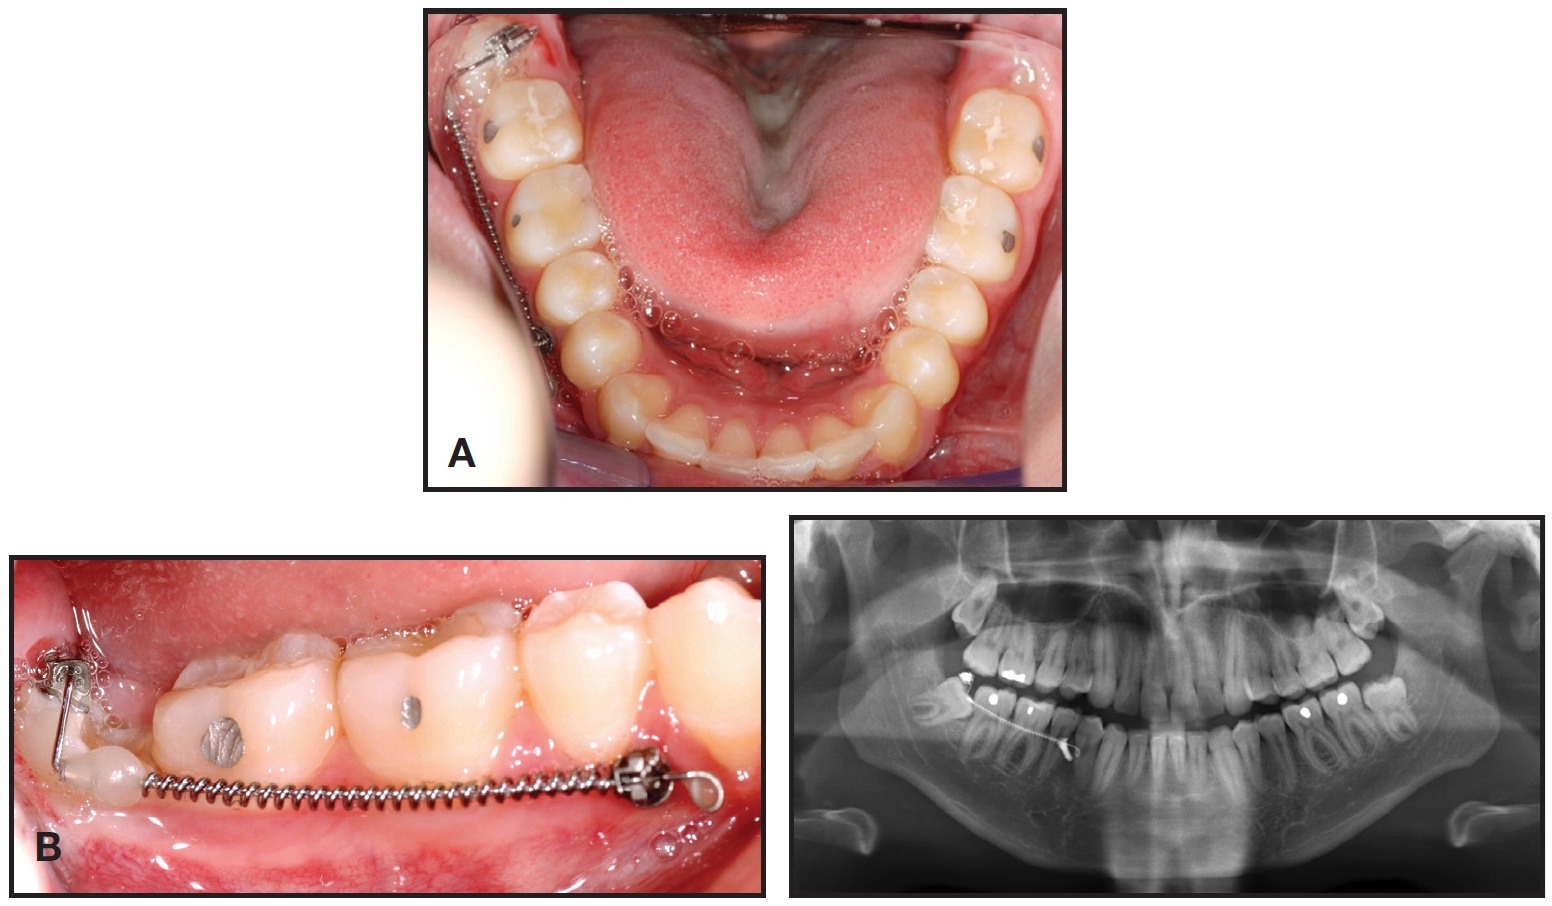

An 18-year-old female had previously undergone orthodontic treatment involving the extraction of four first premolars due to crowding in both arches (Fig. 6).

Fig. 6 Case 2. 18-year-old female patient with mesially impacted lower third molars two years and 10 months after completion of previous orthodontic treatment, when all four first premolars were extracted.

Her treatment had finished two years and 10 months earlier. At the time of our evaluation, the patient's upper third molars had erupted, but the lower third molars were severely mesially impacted. Considering the available space, mini-implants were inserted between the roots of the first molar and second premolar on the right and the canine and lateral incisor on the left. Again, the mechanics described above were implemented (Fig. 7).

Fig. 7 Case 2. A. Activation of uprighting mechanics. B. One month later.

After two years of treatment, both lower molars were upright, and a stable occlusal relationship to the upper molars was achieved (Fig. 8).